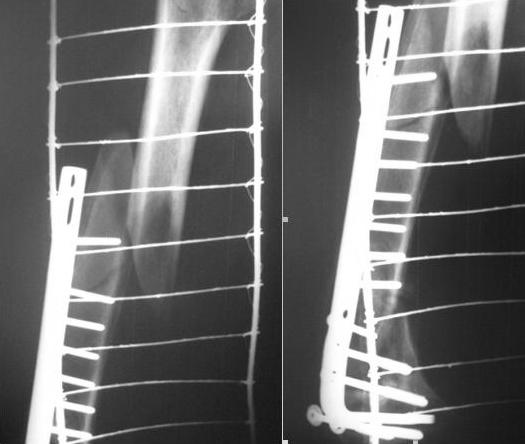

Сегодня на дежурстве поступил пациент с переломом верхней\3 бедренной кости.

Из анамнеза в марте 2008 года оперирован по поводу внутрисуставного перелома дистального

метаэпифиза бедренной кости. Выполнено МОС. На представленных рентгенограммах видно, что

это стресс перелом с формирующимся ложным суставом дистального метафиза. Ваше мнение по

поводу выбора тактики лечения Спасибо за ответ.